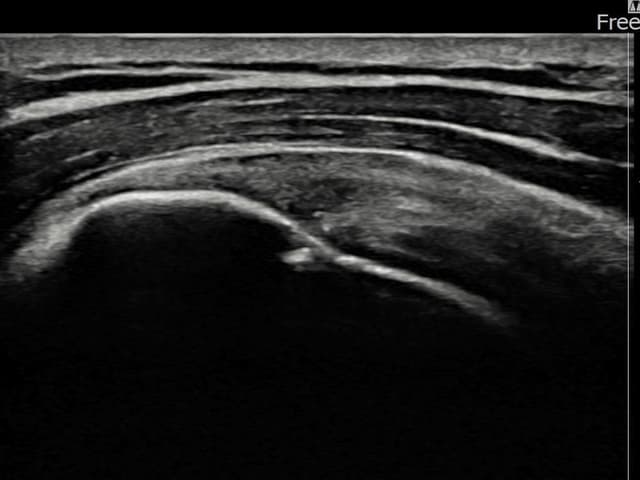

左侧 冈上肌腱 石灰化肌腱炎

16mm × 11mm